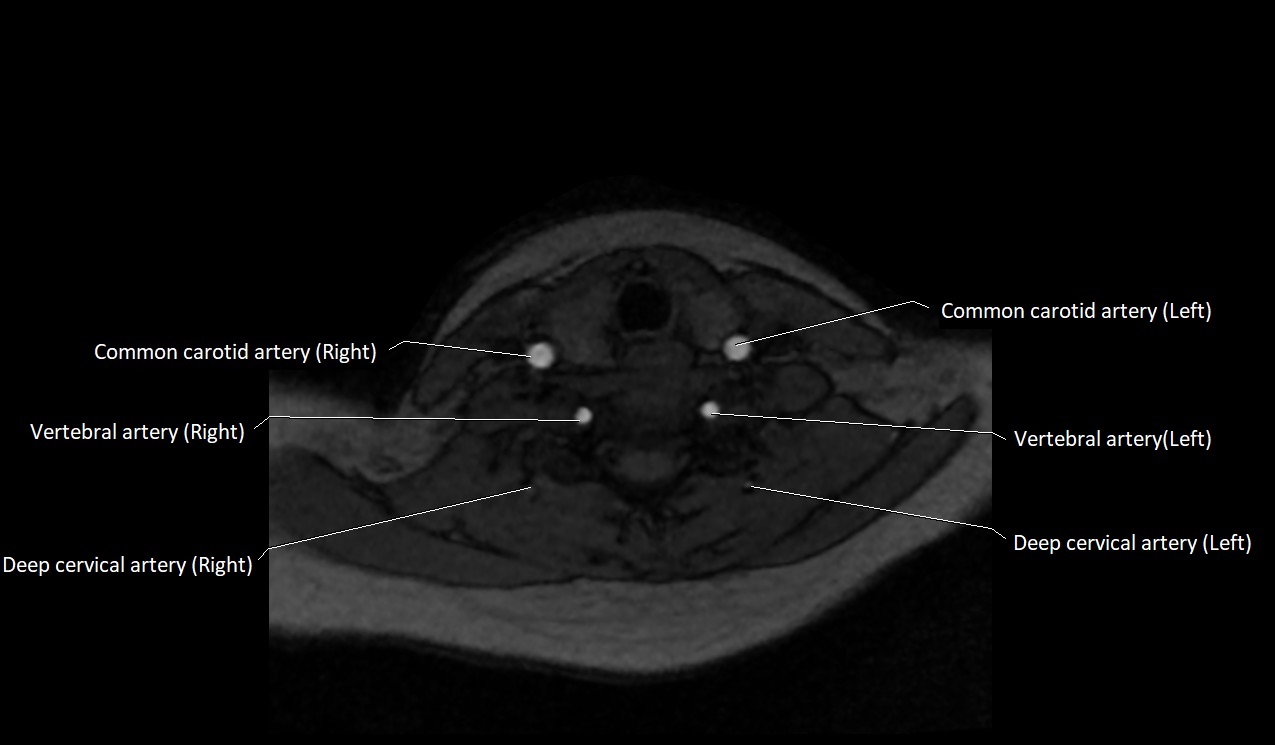

CT Appearance:

• Appears as a small, thin-walled, contrast-enhancing vein in the anterior neck

• Best visualized in the lower neck just lateral to the midline

• Non-contrast CT: difficult to differentiate from surrounding soft tissue, may appear as a hypoattenuating tubular structure

CT image

image